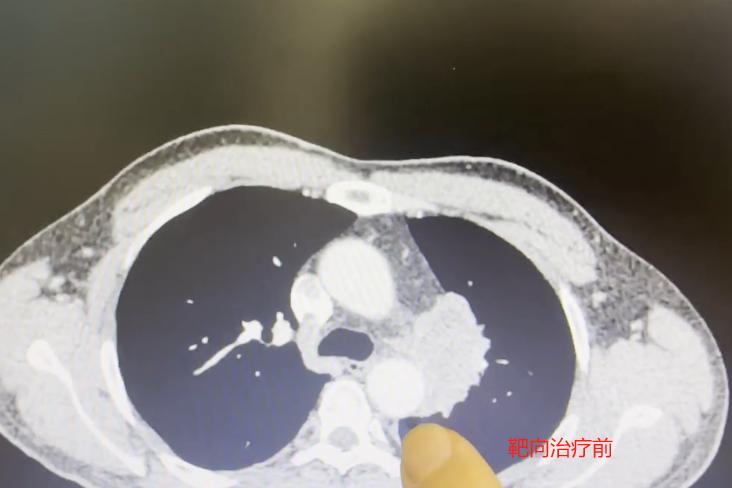

这位患者52岁,抽烟多年,前段时间突然嗓子哑了,一开始还以为是普通感冒引起的,自己吃了点消炎药,没想到不但没好,反而越来越严重...... 他去医院挂了耳鼻喉科,医生检查之后,却建议他再做个胸部CT,这一查,竟查出了中央型肺癌。 好端端的声音嘶哑,怎么会是肺癌?这其实是因为肿瘤长在肺部中央位置,侵犯到了喉返神经,这条神经正好控制着我们的声带活动,一旦受压,声音就会变哑。 所以,当喉镜检查找不到声音嘶哑的原因时,医生通常会建议再查一下胸部CT,排除肺部问题。 不幸中的万幸是,患者后续做了基因检测,发现存在ALK突变,可以用上针对性的靶向药。服药一个月后,复查显示肿瘤明显缩小,连说话声音也清亮了不少。 通过这个病例,也想给大家提个醒: 如果您有长期吸烟习惯、常接触二手烟,或者家里有肺癌家族史,记得定期做早期癌症筛查,别等有症状了再查; 这类高危人群,如果突然出现声音嘶哑,又没有感冒或喉咙痛这类情况,建议先去耳鼻喉科做个喉镜。如果喉镜没问题,就要考虑是不是肺部原因,必要时做个胸部CT。[玫瑰][作揖]MCN双量进阶计划胸外科乔贵宾医生 [心]附:线下免费义诊!11月21日(周五上午),在南方医科大学珠江医院 门诊大厅, 义诊与健康宣教活动来了,欢迎朋友们来参加~